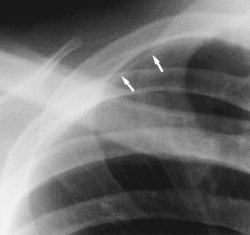

- Scapular companion shadow overlie the scapula, with a smooth, well-defined margin parallel to the medial border of the scapula. The companion shadow results from unusual radiographic position of the scapula, which causes a soft-tissue fold to occur along its medial border. Winging of the scapula may also be responsible for the shadow. Scapular companion shadows may be mistaken for a soft-tissue or pleural lesion.[3]